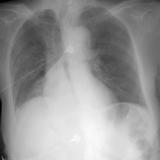

RLL Collapse 1 PA

Date: 02/28/2004

Views: 3445